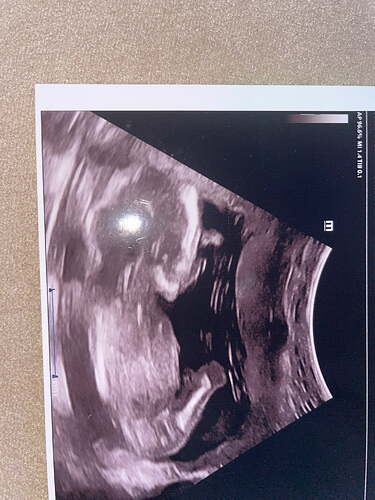

Anladgimdan değil ama erkek hissettim

bence erkek gibi

Erkek gibi

Erkek bebek kesesi gibi balım

Erkek gibii

galiba yuvarlak olanlar kiz yamuk yumuk sekilsizler erkek oluyo sizinki de erkek gibi

Büyük ihtimalle erkek canim

erkek gibi kesesi